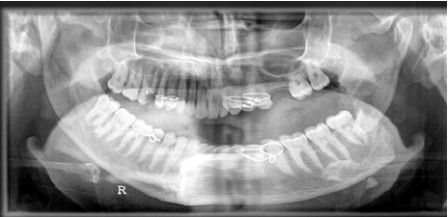

Fig 4: Panoramic radiograph of bilateral angle fracture (sever displacement of the left , , side not associated with third molar)

Only two cases without lower third molar in the fracture site represented sever displacement of the angle fracture (figure 4).